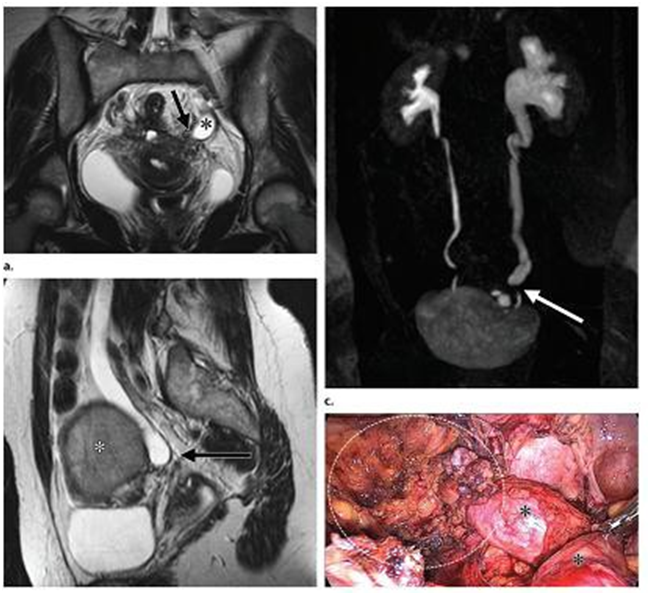

Hình7. Lạc nội mạc quanh cổ tử cung

với hẹp niệu quản trái kèm nang lạc nội mạc buồng trứng trái